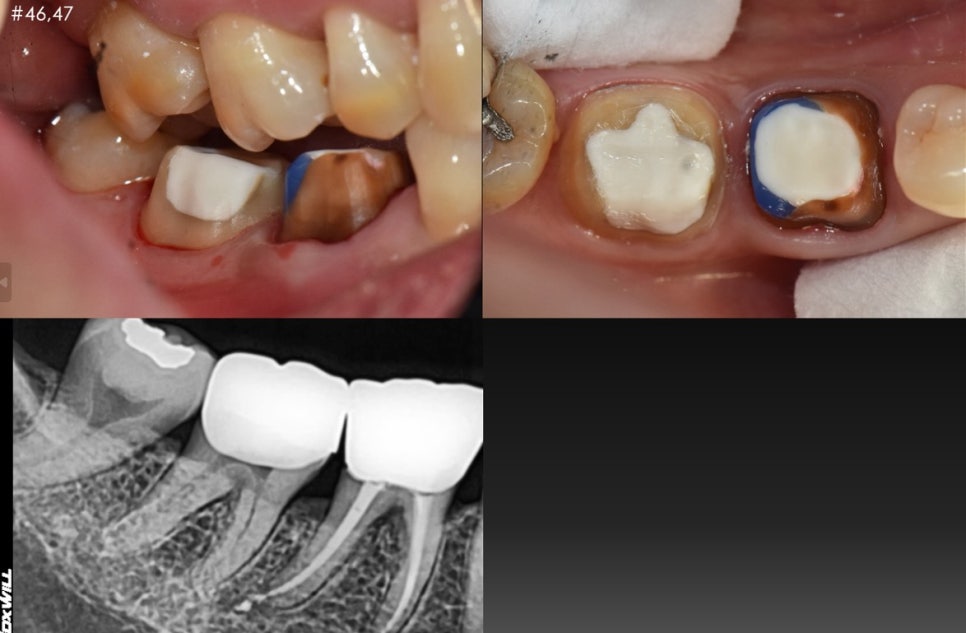

이번 케이스는

저희 아버님이십니다.

과거에도 한번 신경치료 부위가 재발이 돼서

재신경치료 후 보철을 해드렸었는데

거의 10년이 넘어 이번에는

뿌리 쪽 염증과 치주 염증이 복합적으로 생기셨습니다.

이미 뿌리도 녹고 있는 상황이었기 때문에

안타깝지만 아버님께 발치를 설명드리고

대신 염증으로 인해 광범위하게 녹아있는 치조골 주변에

골 이식술을 튼튼하게 하고 임플란트를 완성 시켜드렸습니다^^

치료 시작 : 2022.06.13

치료 종료 : 2022.11.26